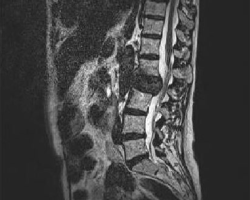

Patient de 74 ans, faiblesse des membres inférieurs depuis 72H avec impossibilité de marcher. Dorso-lombalgies + douleurs costales et du bassin depuis 2 mois. Depuis quelques jours, fourmillements des pieds avec un dérobement des jambes. Toucher rectal nodulaire, dur. Biologiue : Hypercalcémie. Une IRM médullaire en T2 est réalisée en urgence.